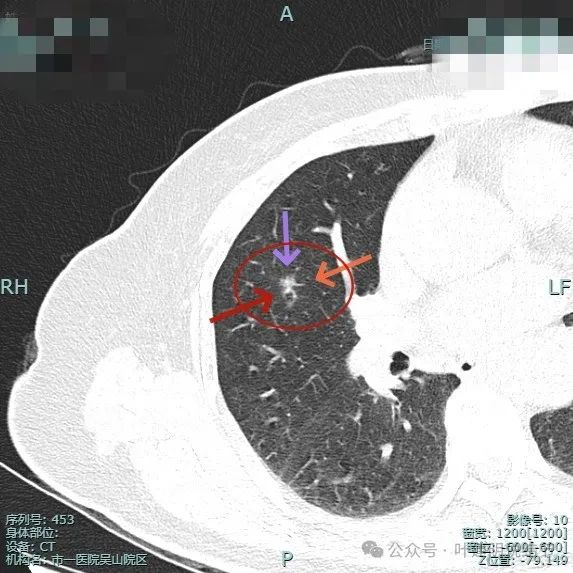

这是2024年4月靶重建时平扫的影像,病灶大小无明显增大,但密度显得较高。

病灶整体显得模糊,但灶内密度不均,有偏实性成分,边缘毛糙,似有小血管走向病灶,轮廓较清楚,瘤肺边界欠清。

病灶紧贴水平裂,而且水平裂略向病灶侧牵拉,灶内有实性成分。虽然瘤肺边界欠清,但整体轮廓仍显得较为清楚。